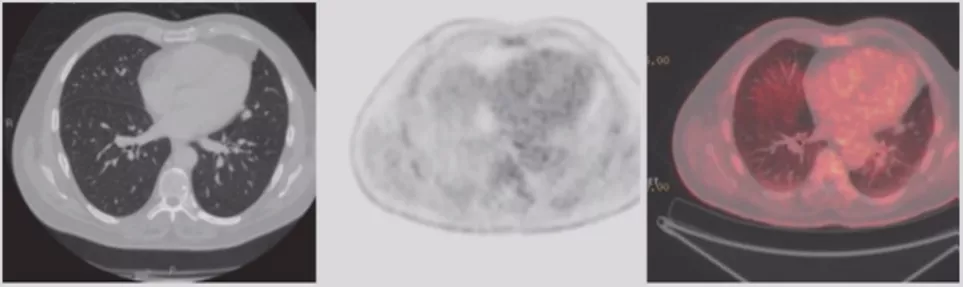

PET-CT

PET-CT对肺结节有一定作用,不同大小、不同类型的肺结节,有不同的诊断价值。但对于纯GGO,PET-CT的诊断价值有限;而对于部分实性GGO,PET-CT有一定价值。指南仅推荐>8mm实性结节或实性成分>8mm且具有高危因素可行PET检查。